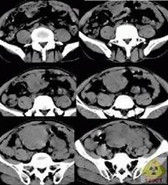

精原細胞瘤多發生於中年以後,常為單側性,右側略多於左側。發生於隱睪的機率較正常位睪丸高几十倍。本瘤為低度惡性。85%的患者睪丸明顯腫大,腫瘤局部侵犯力較低,腫瘤一般有明顯界限。精原細胞瘤發展較慢,一般先轉移至腹膜後淋巴結,後期也可發生廣泛血道播散,確診時,臨床期病例占60%~80%。

精原細胞瘤的病理類型與預後有關,腫瘤擴散的程度和轉移的範圍也影響著預後。故臨床醫生不僅要了解腫瘤的病理類型,而且要根據病變範圍的不同來制定相應的治療方案。因此確定每個患者病變分期是有實際意義的。當今最常採用的分期方法為:

Ⅰ期:腫瘤只局限於睪丸及附睪內,而尚未突破包膜或侵入精索,無淋巴結轉移。

Ⅱ期:由體格檢查、X線檢查證實已有轉移,可擴散到精索、陰囊、髂腹股溝淋巴結,但未超出腹膜後淋巴區域。轉移淋巴結臨床未能捫及者為Ⅱa期,臨床檢查捫及腹腔淋巴結者為Ⅱb期。

Ⅲ期:已有橫膈以上淋巴結轉移或遠處轉移。也有研究者把遠處轉移者歸入Ⅳ期。

任何睪丸腫瘤應先行高位睪丸摘除術,然後根據病理類型和臨床分期選擇治療方案。精原細胞高度放射敏感,較低劑量就能消滅轉移病灶而不產生明顯的放射損傷,臨床Ⅰ期睪丸精原細胞瘤,睪丸高位摘除後,應對同側髂淋巴結和腹膜後淋巴結進行預防性照射,直線加速器高能射線、60Co和千伏X線均可作為外照射源。但不必進行高劑量預防照射。

臨床Ⅱ期睪丸精原細胞瘤的治療

臨床Ⅱa期,腹膜後轉移淋巴結較小,照射野同臨床Ⅰ期;臨床Ⅱb期轉移淋巴結較大,應根據轉移灶大小設計照射野至充分包括淋巴結,腹腔廣泛轉移者,應進行全腹照射。臨床Ⅱ期放射治療劑量分割同臨床Ⅰ期,照射中平面劑量25Gy後,Ⅱa期縮野增強照射轉移淋巴結10Gy,中平面總劑量應達到35Gy/4~5周以上;Ⅱb期增強照射15Gy,總劑量達到40Gy。臨床Ⅱ期睪丸精原細胞瘤,是否需要進行縱隔和左鎖骨上區預防放射,仍有爭議。

臨床Ⅲ期和Ⅳ期睪丸精原細胞瘤的治療

臨床Ⅱ期、Ⅲ期和Ⅳ期睪丸精原細胞瘤均需進行放射與化療的綜合治療,Ⅲ期病例治療方法同Ⅱ期,但縱隔及左鎖骨上區轉移淋巴結的照射劑量應達到35~40Gy/5~6周。臨床Ⅳ期病例治療前已有遠處轉移,應以化療為主,輔以放療控制局部病灶,不作預防性放射。治療以套用化療放療-化療,即“三明治”技術為合理,即先作3個療程化療,爾後照射35~40Gy/5~6周,再進行3~4個療程化療。